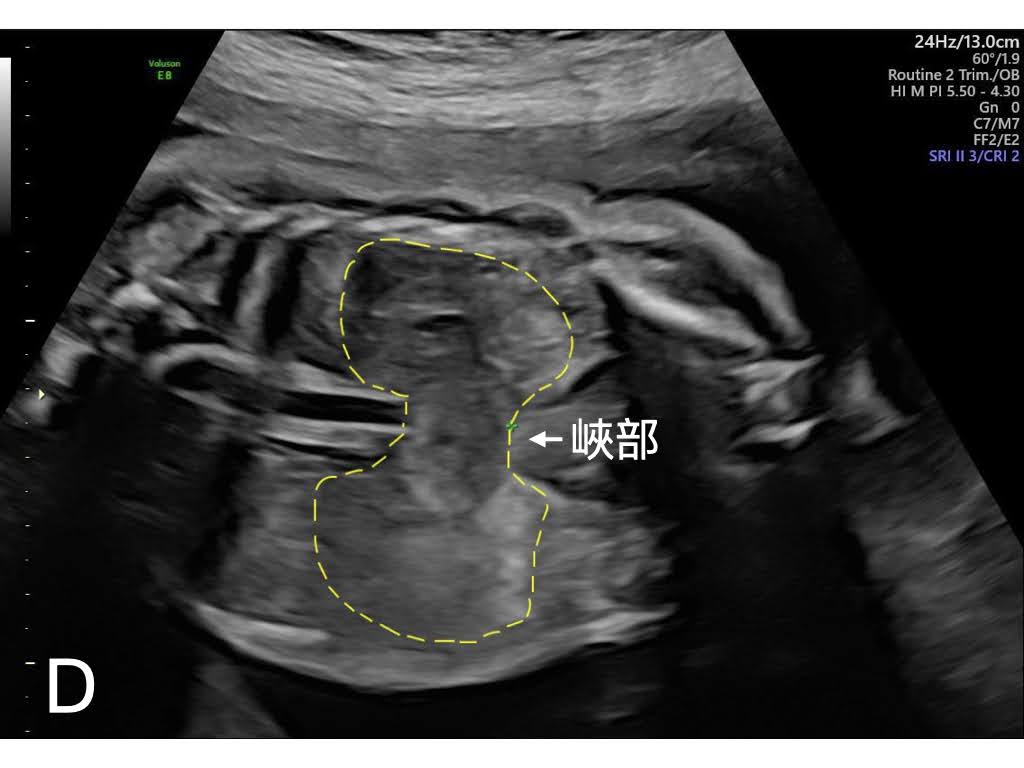

診斷要點如下:取得胎兒呈俯臥姿態(prone position) 時軸向 (axial view) 下的腎臟平面,分別畫出腎盂長軸的延長線,計算雙線間的夾角,即為腎臟腎盂夾角 (Renal pelvic angle)。文章中所納入統計的胎兒,正常腎臟的腎臟腎盂夾角平均角度,在第二孕期及第三孕期,分別為172度及161度;而馬蹄腎組,則是116度及110度,兩組角度上的差異具顯著統計意義。筆者提出,若用「腎臟腎盂夾角角度小於140度」為產前馬蹄腎診斷標準,無論敏感度、特異性、正確性,皆為百分之百,圖二即為台兒診所利用此標準產前診斷的馬蹄腎與正常腎臟的圖示。若希冀在腎臟冠狀切面下(coronal view)辨識出峽部(isthmus)的位置,第三孕期優於第二孕期,或是可考慮安排胎兒磁振造影。

圖二:(D)馬蹄腎的冠狀切面下可見兩腎下極融合的峽部(isthmus)處(台兒診所製作)